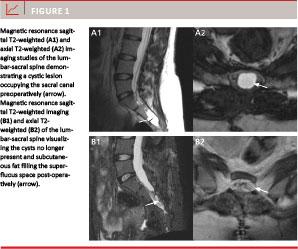

The sacral bone was exposed through a midline incision with the patient in prone position. The posterior wall over the cyst(s) was removed with rongeurs and with careful dissection of the epidural space respecting the cyst(s). Bone chips were preserved. After microsurgical opening of the cyst(s), an attempt was made to identify the CSF fistula. If no CSF fistula could be identified immediately, anti-Trendelenburg posture and modified Quekenstedt maneuver were instituted. In all cases, a fistula was found and a tiny (4-0 or 6-0 vicryl) absorbable tobacco-bag suture encircling the fistula was placed inside the cyst wall, respecting the nerve filaments. The sutured area was covered with a very small piece of muscle and fibrin glue before gentle tightening of the suture. The remaining wall of the cyst(s) was then filled with subcutaneous fat, more fibrin glue was added and the cyst was sutured (Figure 11). The exposed area of dura and the nerve roots were then covered with a double layer of polyanhydroglucuronic acid products and fibrin glue and on top a fair layer of bone chips was replaced in the osseous defect. Finally, fascia, subcutaneous tissues and skin were closed separately with absorbable sutures after final control of haemostasis. No drains were used.